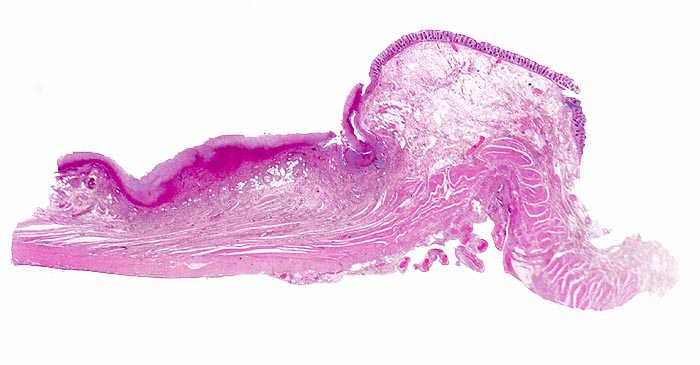

Basel 3BA HS/ Pseudomembranöse Enterokolitis

Pseudomembranöse Enterokolitis

Morphologische Merkmale:

• Herdförmige Schleimhautnekrosen.

• In den Nekrosezonen pilzförmige Pseudomembranen bestehend aus nekrotischem Detritus, Entzündungszellen und Fibrin.

• Zwischen den Pseudomembranen normale Kolonschleimhaut. Das sollte der Kliniker dem Pathologen mitteilen: